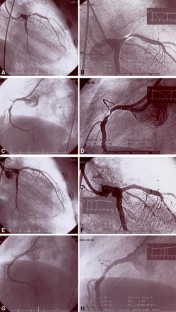

Percutaneous Transluminal Coronary Angioplasty for Coronary Arterial Stenosis in a 10-Year-Old Boy with Kawasaki Disease and a Brief Review

A 10-year-old boy developed coronary artery stenosis 9 years after suffering Kawasaki disease with coronary artery aneurysms at the age of 7 months old. Percutaneous transluminal coronary angioplasty was performed successfully to dilate the coronary arteries in order to prevent obstruction of the coronary arteries.

Fig. 1